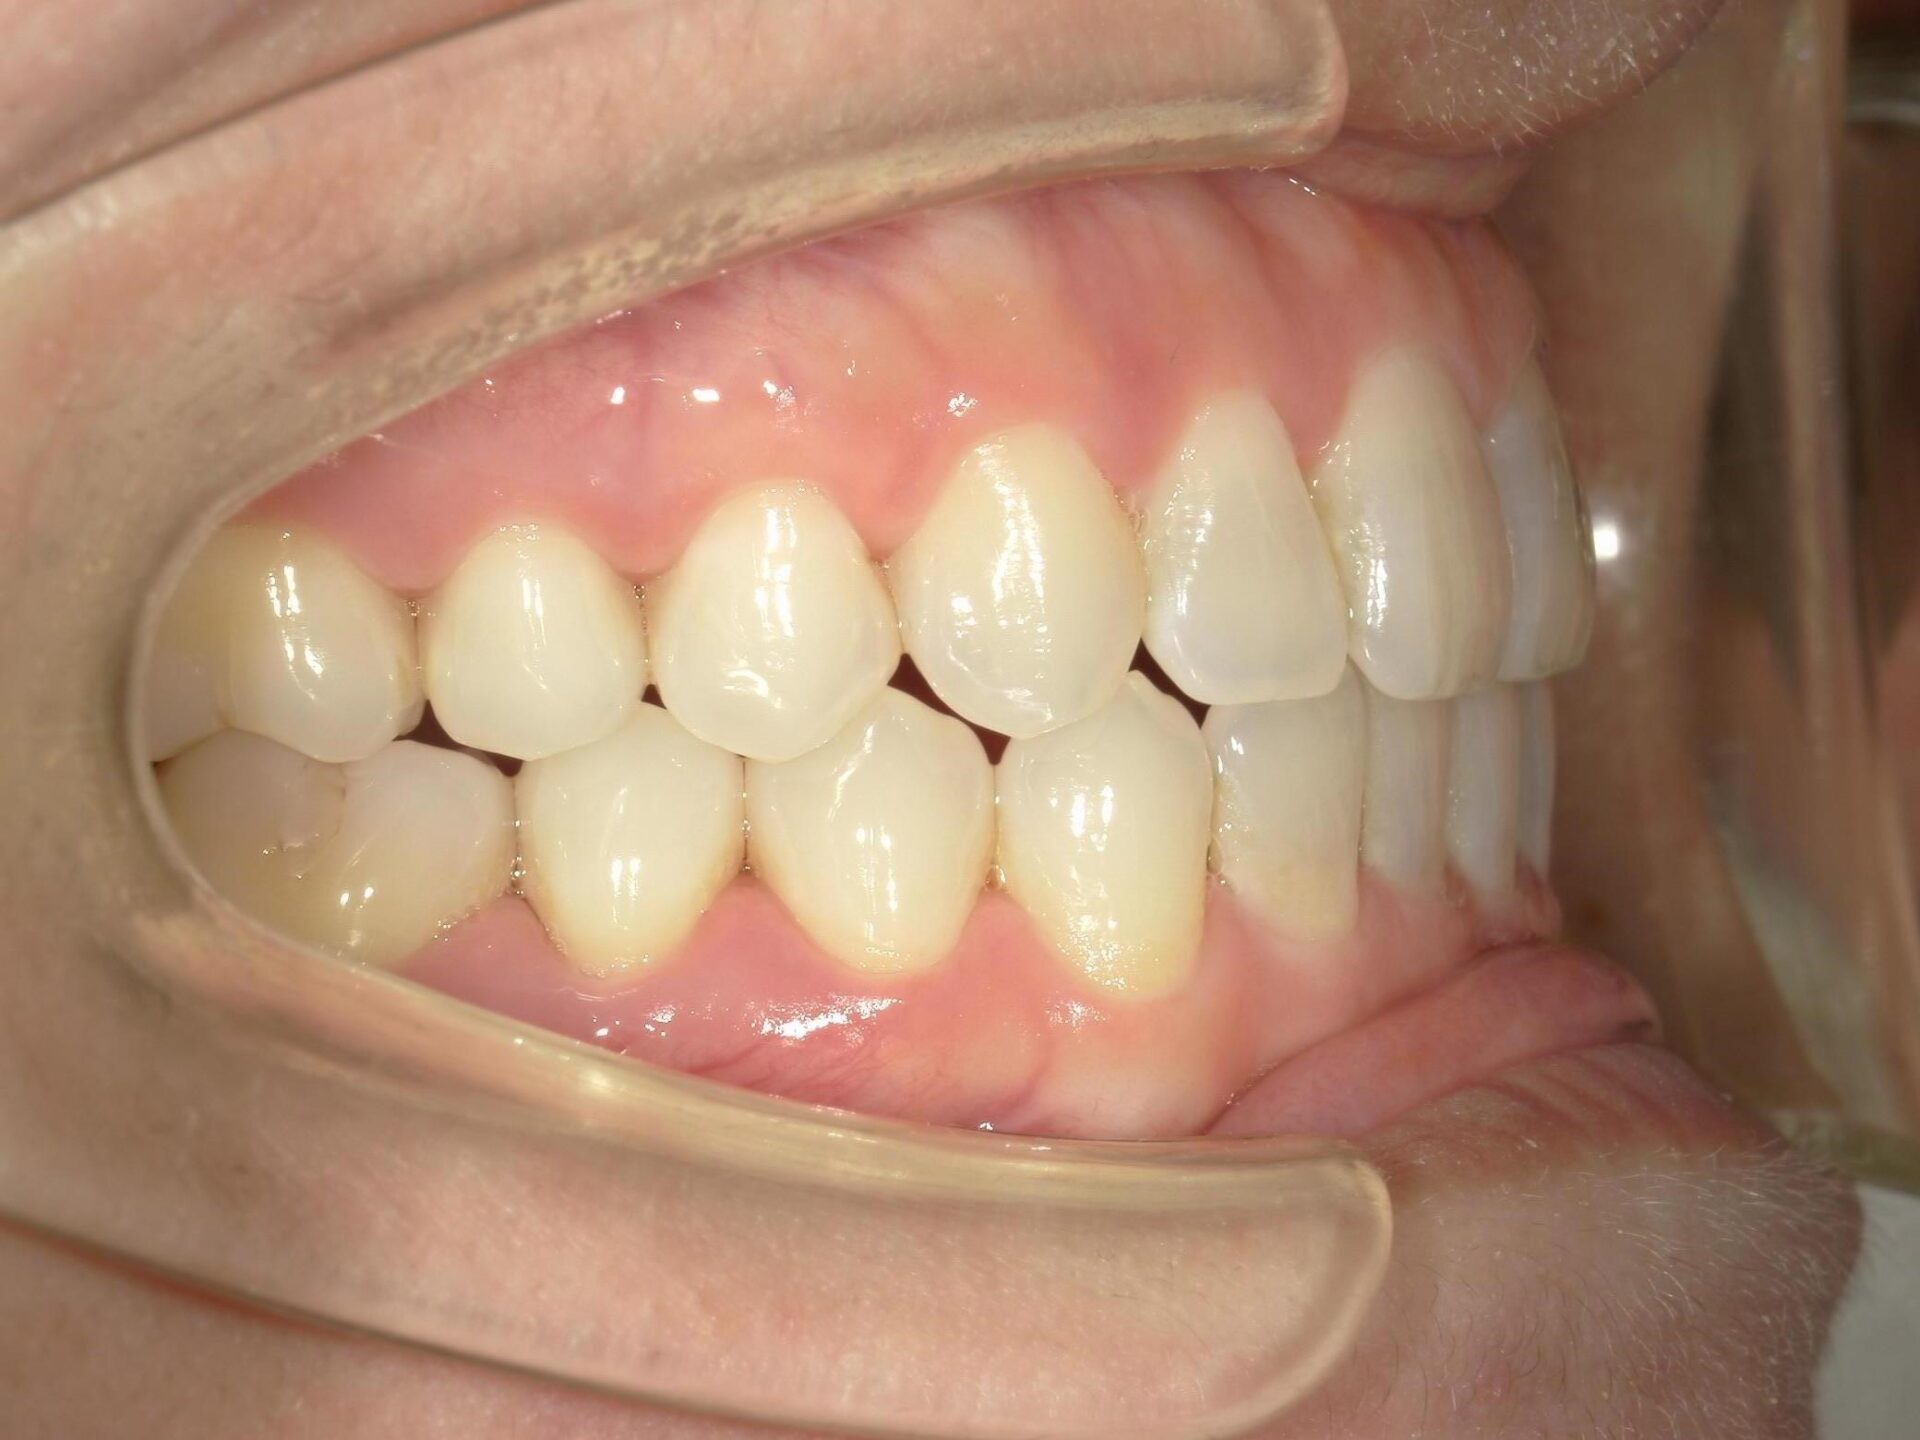

30代、女性、ワイヤー

| 施術内容 | 主訴:歯と歯の先端が噛んでしまいすり減ってきた 詳細:マウスピース矯正を装着しての歯並び改善 |

| 治療期間 | 6ヶ月(11/19現在 治療終了) |

| リスク・副作用 | ■リスク・副作用 ・治療の初期段階では、痛みや不快感が生じやすくなりますが、一週間前後で慣れます。 ・歯の動き方には個人差があるため、予想された治療期間より延長する場合があります。 |

| 費用 | 12枚コース 32万(税込352,000円) |